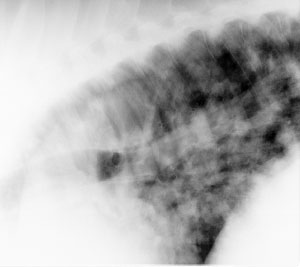

A radiograph (lateral view) of the caudal thorax is shown. Which of the following is a correct description of the radiologic findings?